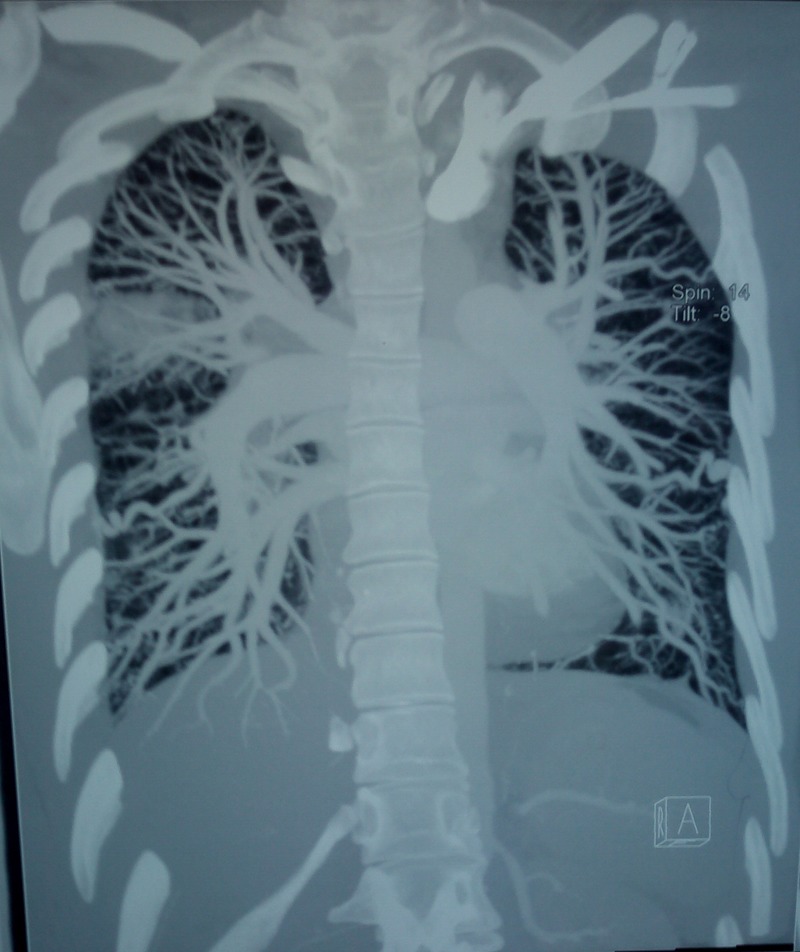

Figure 4.

Spiral CT sagittal reconstruction images showing right upper lobe consolidation and bilateral pulmonary arteriovenous malformations in the lower lobes.

Routine investigations revealed normal haematological, biochemical and coagulation parameters. A chest radiograph showed patchy consolidation in the right upper zone in addition to the features of PAH (figure 1). The sputum Ziehl Neelsen stain was negative for acid-fast bacilli and the tuberculin test was negative. Fibreoptic bronchoscopy showed a normal trachea-bronchial tree. Bronchoalveolar lavage yielded mildly haemorrhagic fluid which was negative for AFB, fungal and malignant cytology. Serological tests for HIV, connective tissue disorders and systemic vasculitis were negative. Two-dimensional echocardiography showed a dilated right ventricle and right atrium and moderate tricuspid regurgitation with moderate PAH (pulmonary artery systolic pressure—67 mm Hg). piral CT angiography showed a dilated main pulmonary artery due to PAH and bilateral numerous pulmonary arteriovenous malformation (PAVM) in the upper and lower lobes with an area of ground glass opacity due to pulmonary haemorrhage in the right lower lobe (figures 2–4). Ultrasonography of the abdomen, gastro-duodenoscopy and MRI brain done did not reveal any other AV malformations. Cardiac catheterisation indicated a mean pulmonary artery pressure of 54 mm Hg (72/40/54 mm Hg) and increased pulmonary vascular resistance (5.6 Wood units), with normal pulmonary capillary pressure (12 mm Hg) and an elevated cardiac index (5.5 l/min/m2). Screening of family members for AVM was negative. Genetic mutation analysis was not performed in this case due to financial constraints.